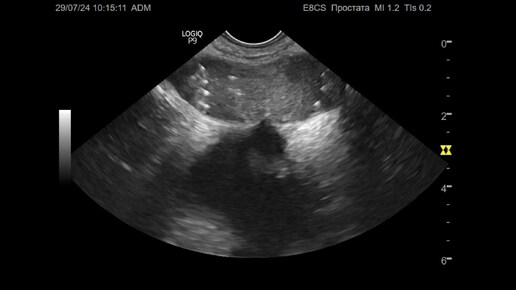

Ультразвуковая диагностика (УЗИ). Доктор Иогансен. Видеопримеры. Выпуск 90. Предстательная железа после брахитерапии.